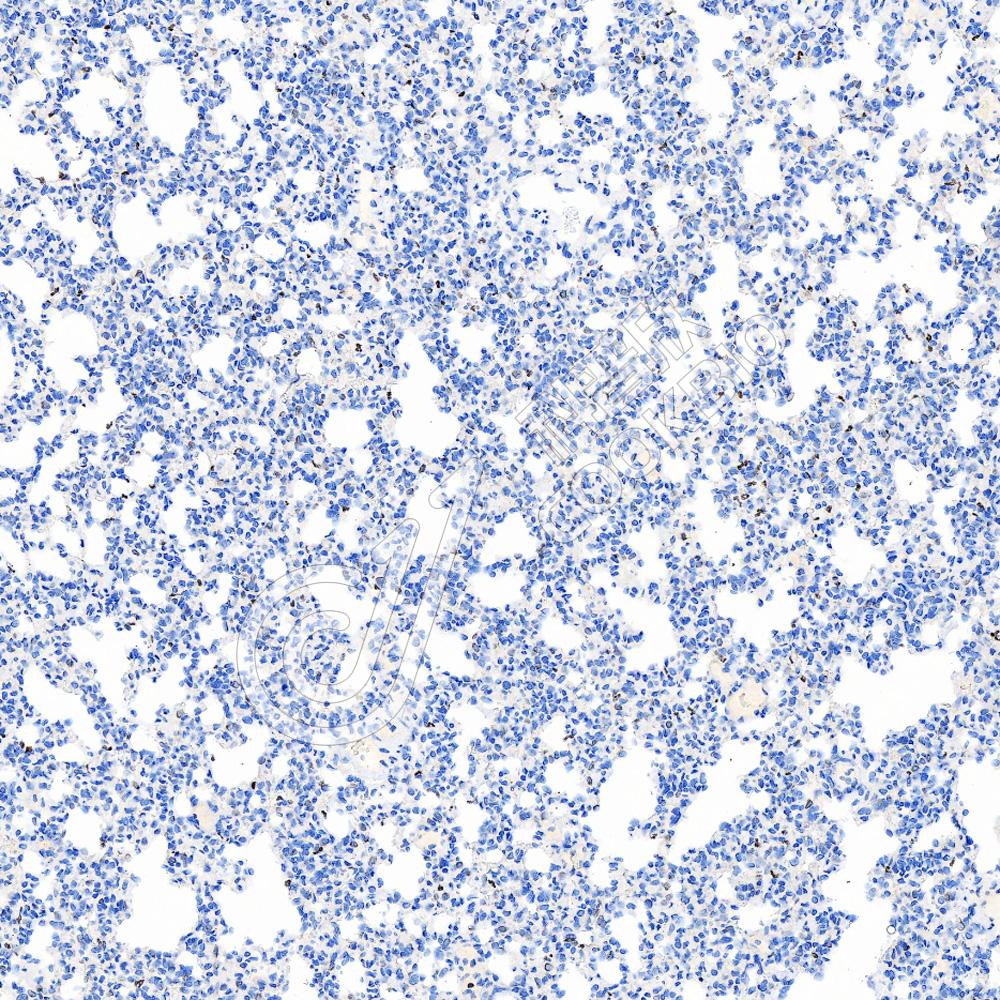

IHC检测PADI4/PAD4蛋白(货号 K5450306).

样品: 人扁桃体, 4%多聚甲醛 (货号KSG1101) 固定12-24小时.

抗原修复: Tris-EDTA抗原修复液(pH 9.0) (货号KSG1203), 水浴100℃, 25分钟.

—抗: 1: 600稀释, 4℃ 孵育过夜.

二抗: S-vision免疫组化多聚二抗(山羊抗兔),即用型 (货号KB3906), 室温孵育20分钟.